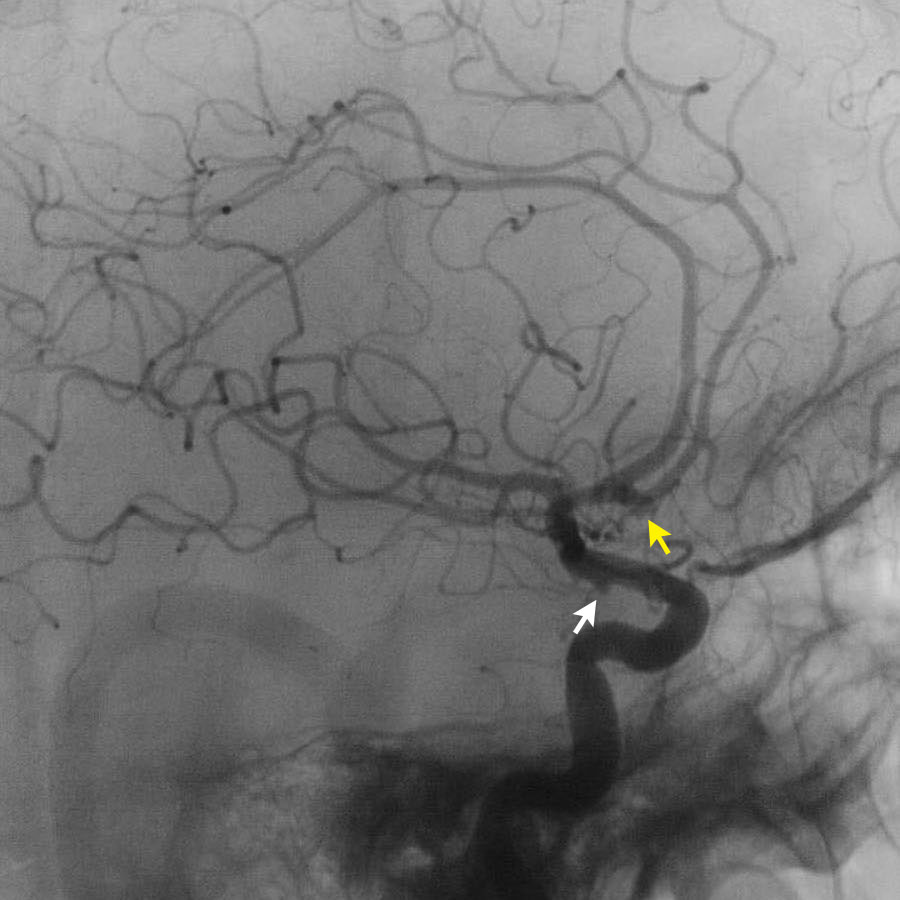

Các hình ảnh cho thấy DSA trước và sau khi đặt coil túi phình.

PICA, nidus và các tĩnh mạch dẫn lưu bất thường (cùng tạo thành AVM) vẫn còn ngấm thuốc tương phản.

Quyết định không điều trị trực tiếp AVM mà lựa chọn theo dõi và có thể can thiệp phẫu thuật trong tương lai.